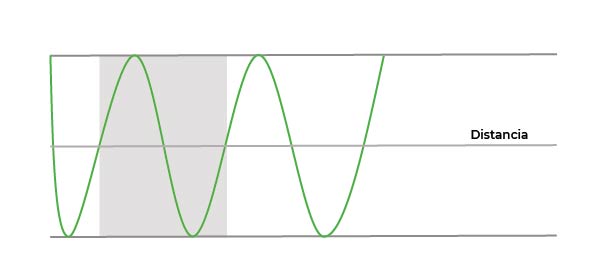

Distancia

Podemos representar estas ondas en función de la distancia que recorren: